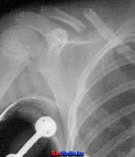

Иық сүйегінің айдаршық үсті сынығы